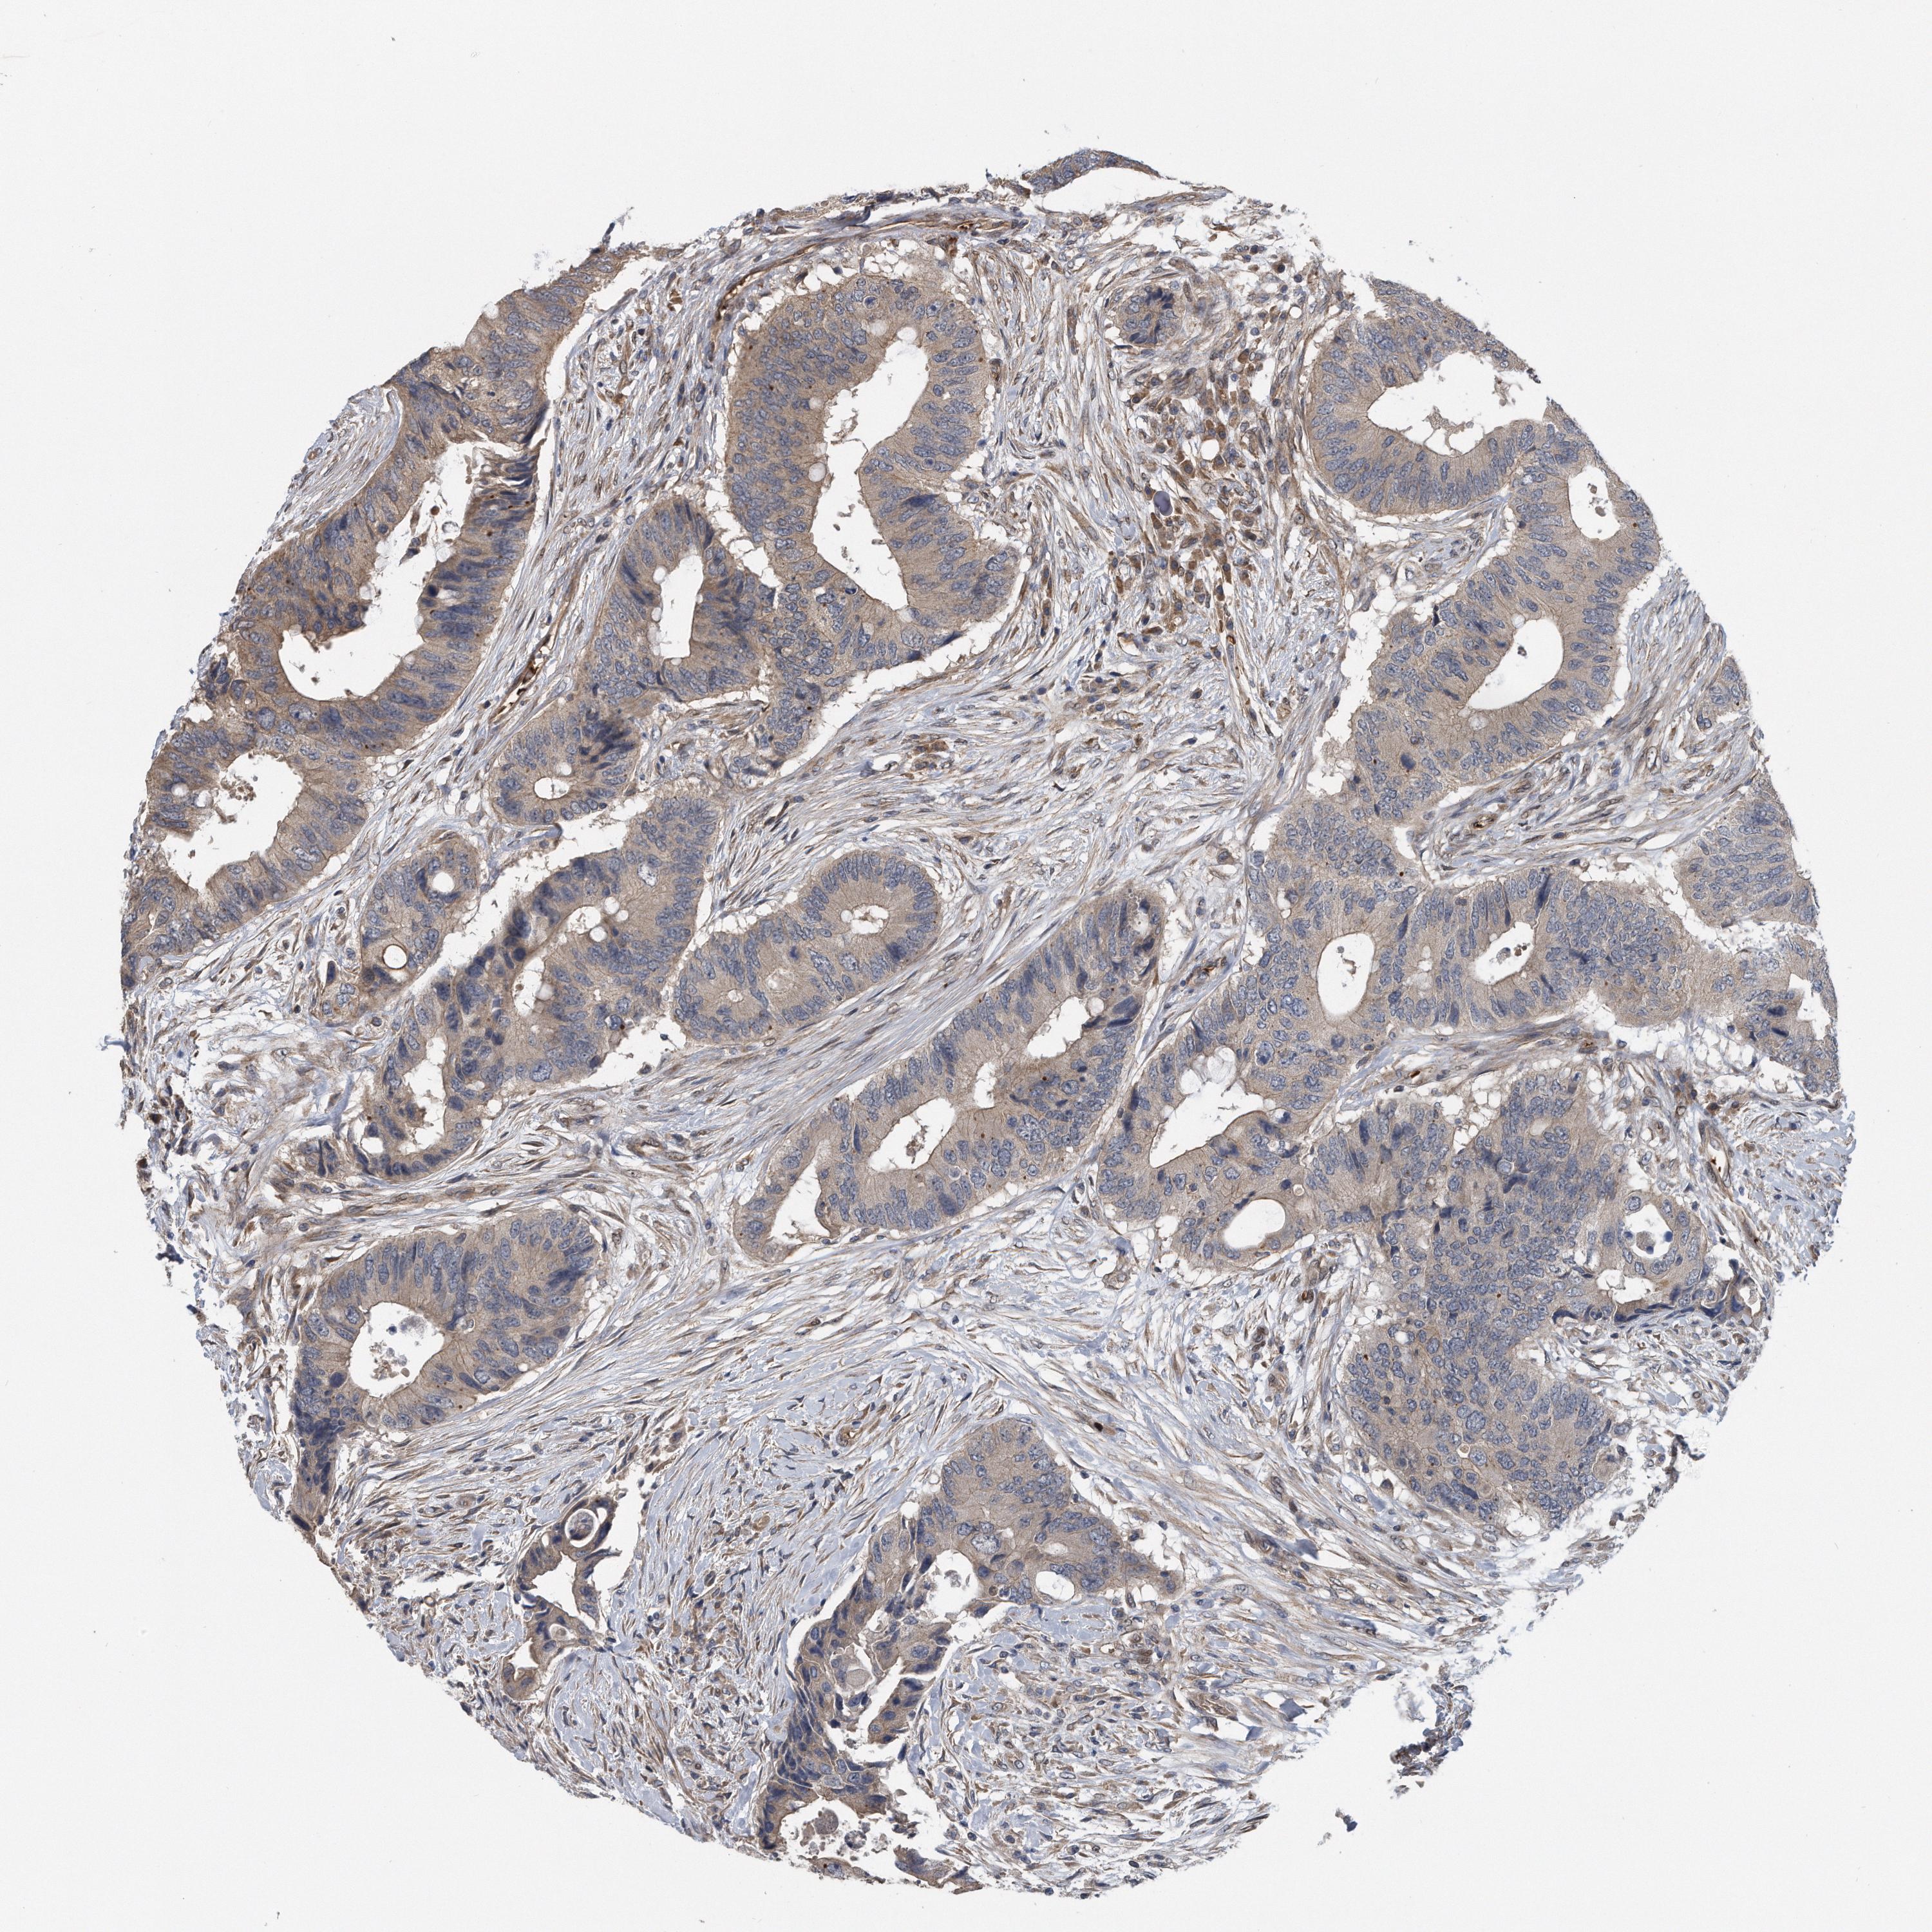

RECTUM ADENOCARCINOMA (TCGA) - Interactive survival scatter ploti

The Survival Scatter plot shows the clinical status (i.e. dead or alive) for all individuals in the patient cohort, based on the same data that underlies the corresponding Kaplan-Meier plots. Patients that are alive at last time for follow-up are shown in blue and patients who have died during the study are shown in red.

The x-axis shows the expression levels (FPKM) of the investigated gene in the tumor tissue at the time of diagnosis. The y-axis shows the follow-up time after diagnosis (years). Both axes are complimented with kernel density curves demonstrating the data density over the axes. The top density plot shows the expression levels (FPKM) distribution among dead (red) and alive patients (blue). The right density plot shows the data density of the survived years of dead patients with high and low expression levels respectively, stratified using the cutoff indicated by the vertical dashed line through the Survival Scatter plot. This cutoff is automatically defined based on the FPKM cutoff that minimizes the p-score. The cutoff can be changed by dragging the vertical line or by entering a cutoff value in the square labeled "Current cut-off".

Under the Survival Scatter plot the p-score landscape (black curve; left axis) is shown together with dead median separation (red curve; right axis). Dead median separation is the difference in median mRNA expression between patients who have died with high and low expression, respectively. It is calculated as follows: median FPKM expression of dead patients with high expression - median FPKM expression of dead patients with low expression. This is intended to aid the user in visually exploring custom cutoffs and the associated p-scores and dead median separation.

Individual patient data is displayed and can be filtered by clicking on one or more of the category buttons on the top of the page. Categories describing expression level and patient information include: high, low, alive, dead, female, male and tumor stages. The scale of the x-axis can be toggled between linear and log-scale by clicking on the "x log" button. Mouse-over function shows TCGA ID, patient information and mRNA expression (FPKM) for each patient.

& Survival analysisi

Kaplan-Meier plots summarize results from analysis of correlation between mRNA expression level and patient survival. Patients were divided based on level of expression into one of the two groups "low" (under cut off) or "high" (over cut off). X-axis shows time for survival (years) and y-axis shows the probability of survival, where 1.0 corresponds to 100 percent.

ZNF79 is not prognostic in Rectum Adenocarcinoma (TCGA)

Best expression cut offi

Based on the FPKM value of each gene, patients were classified into two groups and association between prognosis (survival) and gene expression (FPKM) was examined. The best expression cut-off refers the FPKM value that yields maximal difference with regard to survival between the two groups at the lowest log-rank P-value. Best expression cut-off was selected based on survival analysis .

When clicking on this number, the vertical dashed line indicating cut-off, the interactive survival plot, and the Kaplan-Meier curve will be adjusted to show results based on the best expression cut-off.

: 2.4

TCGA RNA samplesi

RNA-seq data is reported as average FPKM (number Fragments Per Kilobase of exon per Million reads), generated by the The Cancer Genome Atlas (TCGA) .

Normal distribution across the dataset is visualized with box plots, shown as median and 25th and 75th percentiles. Points are displayed as outliers if they are above or below 1.5 times the interquartile range. FPKM values of the individual samples are presented next to the box plot.

Average pTPM 2.6

Number of samples 88